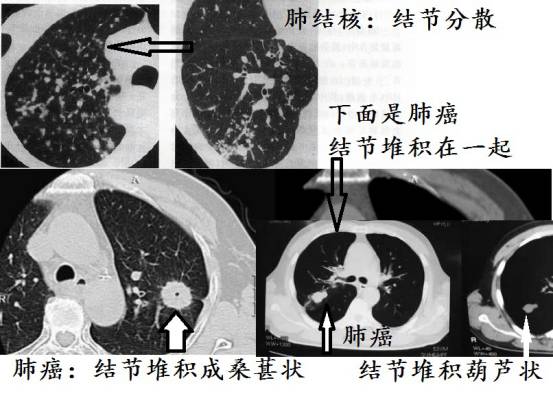

结节一般不会堆积在一起

肺结核的光棍特征,肺结核虽然子满天下,但是不像肿瘤喜欢同性恋(多个结节堆积在一起),肺结核的小结节常常分散在两肺,各玩各的,各自为政!